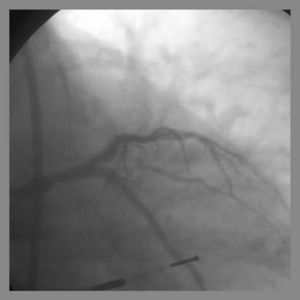

2) Both the parent and side branch are wired. Predilation is recommended to ensure optimal balloon expansion and ease stent delivery. It is important to identify which wire is placed in which branch. We recommend either using 2 separate colored guide wires, keeping a marker on 1 wire, or covering a wire with a sterile towel while not in use.

5) The 2nd stent is advanced into the parent vessel and placed across the side branch.

6) The side branch stent is deployed. (Another option is to place a balloon in the parent branch and inflating to low atm while pulling the side branch back. This may help ensure adequate coverage of the ostium.